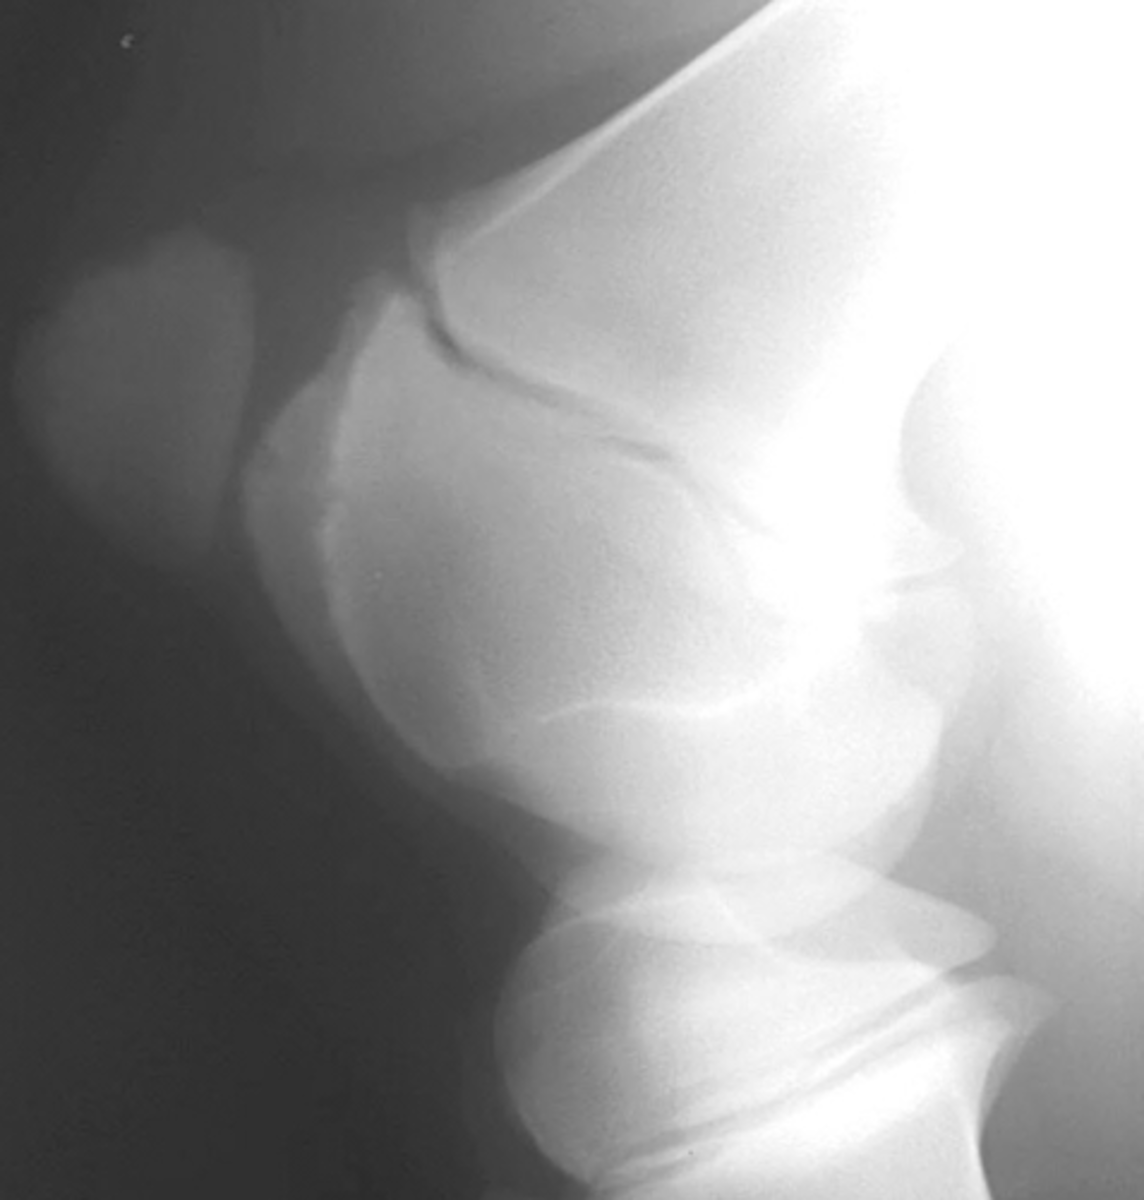

Nothing this is a normal neonatal foal radiograph

What is the problem w/ this radiograph?